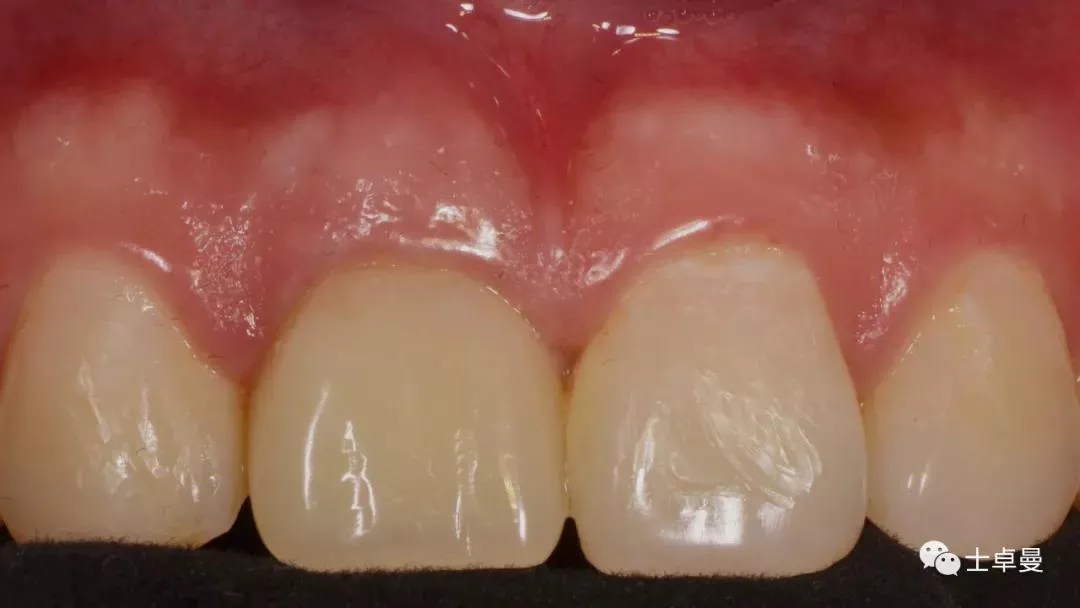

临时修复后2个月,龈缘及龈乳头位置理想,软组织健康

· 2个月后,见唇侧骨弓轮廓可,龈缘及龈乳头形态自然,去11临时修复体,植体ISQ值测定82,个性化取模,试戴Variobase氧化锆基台+LAVA氧化锆单冠,就位被动性良好,增加基台扭力至35Ncm,粘接固位上部冠,调合抛光。

完成永久修复,骨弓轮廓、龈缘及龈乳头形态自然,可见牙龈点彩,修复体外形及色泽可,患者满意。